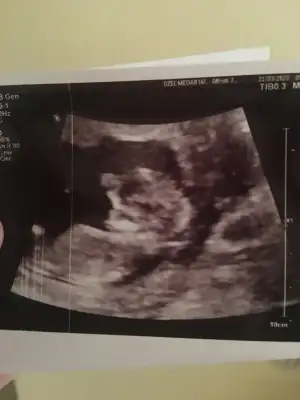

Merhaba yeni uyeyim elimde 7 haftalik karindan 10 haftalik alltan ulturason goruntusu var cinsiyet tahmini yapabilirmisiniz acaba şimdiden teşekkurler ilk resim 7 hafta karin son resim 10 haftta altan bakildi.

Keseye göre erkek ama tutmayabilir siz 11 12 13 haftaları paylaşın